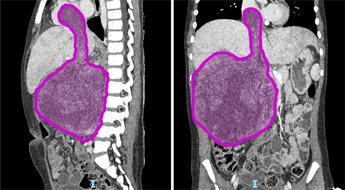

(Adnkronos) – Sei cicli di chemioterapia, poi nove ore di intervento ma ora il tumore di circa 1,5 chili di cui era affetta Sara (nome di fantasia), a soli otto anni, è stato rimosso. "Un intervento chirurgico complesso e straordinario", ha spiegato in una nota l'ospedale pediatrico Bambino Gesù di Roma dove è stata operata la bambina. "Questo successo non è solo una vittoria medica, ma anche una grande speranza per tante famiglie che affrontano situazioni simili", ha affermato Alessandro Crocoli, responsabile dell’Unità di Chirurgia Oncologica. "Sara (nome di fantasia), 8 anni appena compiuti, era affetta da un nefroblastoma al rene destro che si estendeva all’interno della vena renale, della vena cava inferiore fino a raggiungere l’atrio destro del cuore, a causa di una trombosi neoplastica. Questa rara estensione del tumore – ha spiegato l'ospedale – si verifica in appena il 4-10% dei casi di nefroblastoma. Prima dell’intervento Sara è stata sottoposta a sei cicli di chemioterapia, eseguiti dal team di oncologi guidati dal professor Franco Locatelli, per ridurre la massa tumorale e facilitare l’operazione. La fase preparatoria pre-chirurgica si è avvalsa di tecniche all’avanguardia di diagnostica per immagini come l’elaborazione 3D del tumore da asportare realizzata dall’unità di Imaging avanzato cardiotoracovascolare e fetale". "L’intervento, reso possibile dalla collaborazione tra oncologi, chirurghi, cardiochirurghi, e anestesisti, rappresenta un risultato importante per la medicina pediatrica", ha reso noto l'ospedale pediatrico Bambino Gesù. L’operazione ha avuto una prima fase in cui l’équipe di chirurgia oncologica, formata dal dottor Alessandro Crocoli e dalla dottoressa Chiara Grimaldi, ha rimosso il rene destro, "il cui volume era dieci volte superiore rispetto alla norma a causa del tumore. Successivamente i cardiochirurghi, guidati dal professor Lorenzo Galletti e con il dottor Gianluca Brancaccio come primo operatore, hanno temporaneamente arrestato il cuore della bambina, mantenendola in vita con la circolazione extracorporea, per rimuovere la parte del tumore che aveva invaso l’atrio destro – prosegue la nota dell'ospedale del Vaticano – Infine, dopo aver riavviato il cuore, i chirurghi hanno completato l’operazione rimuovendo il residuo tumorale dalla vena cava inferiore. In totale, il tumore asportato pesava circa 1,5 kg. La parte anestesiologica del complesso intervento, durato più di 9 ore, è stata gestita dal team della Terapia Intensiva Cardiochirurgica del dottor Luca Di Chiara". "Questo successo non è solo una vittoria medica, ma anche una grande speranza per tante famiglie che affrontano situazioni simili: rappresenta un traguardo straordinario nella chirurgia oncologica pediatrica. Rimuovere un tumore di queste dimensioni, così invasivo, è stato possibile solo grazie a una pianificazione chirurgica estremamente accurata e alla collaborazione di un’équipe multidisciplinare altamente specializzata – ha detto Alessandro Crocoli, responsabile di Chirurgia Oncologica – La priorità è stata garantire il miglior risultato possibile, con un approccio personalizzato e sicuro". "L’asportazione della massa tumorale che invadeva il cuore ha richiesto l’arresto cardiaco e l’uso della circolazione extracorporea, procedure complesse che esigono il massimo coordinamento – ha commentato il professor Lorenzo Galletti, responsabile di Cardiochirurgia – Questo intervento dimostra come, unendo competenze avanzate e tecnologia d’avanguardia, possiamo affrontare anche i casi più difficili, restituendo speranza ai nostri giovani pazienti". Dopo una breve degenza in terapia intensiva, Sara "sta proseguendo la convalescenza in modo positivo e riceve le cure necessarie per un recupero ottimale. La scorsa settimana ha festeggiato il suo ottavo compleanno in reparto con la famiglia e con i medici che si stanno prendendo cura di lei. Il suo percorso di cura continuerà con sedute di radioterapia addominale e ulteriori cicli di chemioterapia", conclude l'ospedale. Il nefroblastoma, noto anche come tumore di Wilms, "è una neoplasia rara che colpisce prevalentemente i bambini tra 1 e 5 anni, con un picco tra i 2 e i 3 anni. Rappresenta circa il 90% dei tumori renali pediatrici, anche se i tumori al rene costituiscono meno del 5% delle neoplasie in età pediatrica – ricorda l'ospedale – In Italia, la sua incidenza è di circa 8 casi ogni milione di bambini. I reni si formano durante lo sviluppo embrionale a partire da alcune particolari cellule staminali dette progenitrici. In alcuni casi, queste cellule persistono nei reni dopo la nascita e, a causa di mutazioni genetiche, possono proliferare in modo incontrollato, portando alla formazione del nefroblastoma". —cronacawebinfo@adnkronos.com (Web Info)